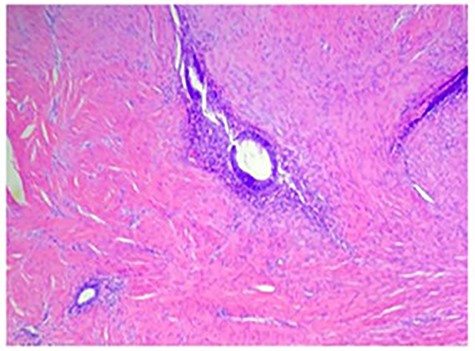

Permanent pathologic analysis revealed fibroadipose tissue with interspaced endometrial glands and stroma, consistent with endometriosis. No endometriosis was identified at the margins. H&E stain of the mass is shown in Fig. 3.

H&E stain demonstrating fibroadipose tissue with interspaced endometrial glands and stroma consistent with endometriosis.